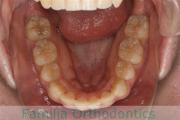

No.22V-029

- 叢生

- 上顎前突

- 19歳

- 男性

- 抜歯部位

- 上:

- 8448

- 下:

- 主な使用装置:

- FEA 022

- 治療にかかった費用:

- 92万円

でこぼこを治したいということで来院されました。上下左右から親知らずも第一小臼歯も抜歯が必要で、歯科矯正アンカースクリューを併用して大臼歯を後ろに引っ張りながらの治療でした。3年弱、35回程度の通院が必要でした。

叢生が著しく、後戻りのリスクがあります。またアンカースクリューが必須のため、もしもスクリューが安定しないと、治療が難しく長くなってしまう恐れがありましたが、幸い脱落は見られませんでした。

- ≫治療前

-

上顎

下顎